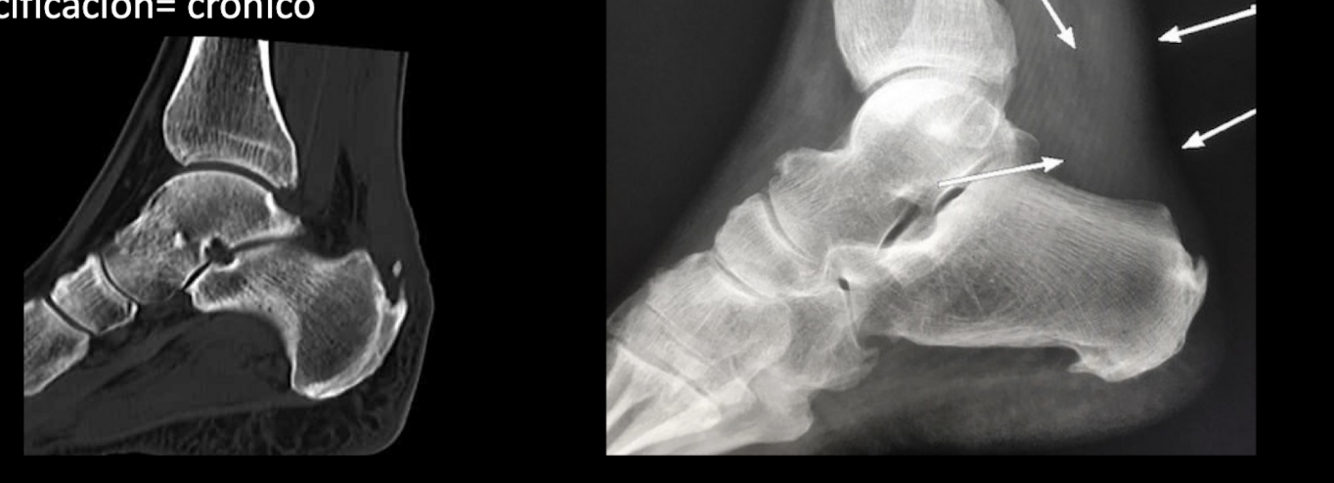

RX Y TC RTAQ

A

Edema de tx blando

borramiento triangulo graso de kager

descartar avulsión calcánea

calcificación: crónico